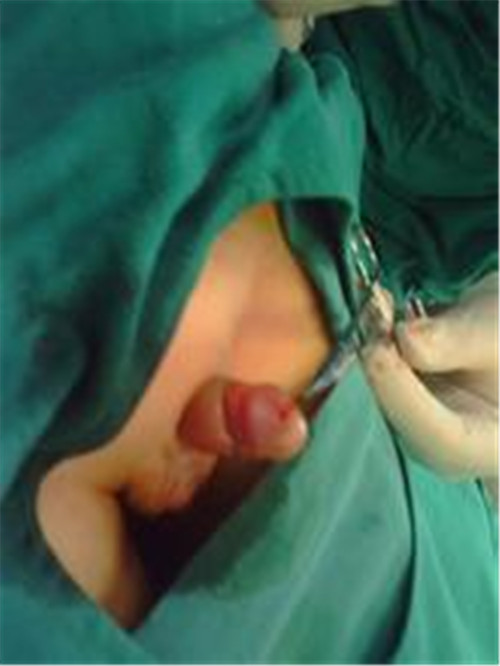

蛙式治療尿道下裂